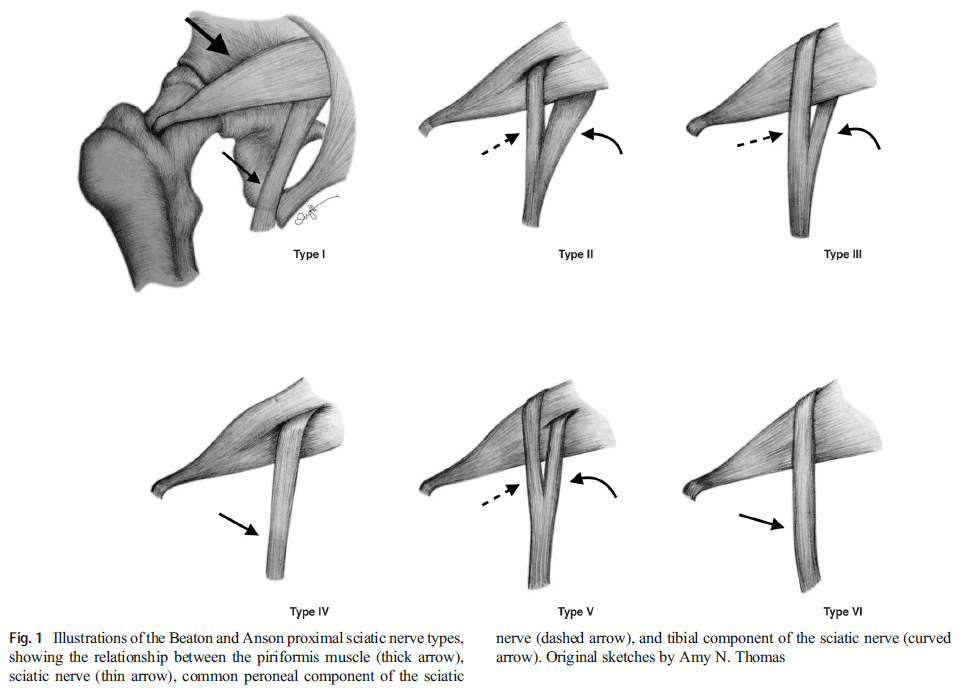

Piriformis-muskeln löper från korsbenet till höftleden. Eftersom ischiasnerven löper under piriformis föreslogs det att en stram piriformis kunde komprimera ischiasnerven och orsaka smärta i skinkan och på baksidan av benet. Forskare har till och med hittat anatomiska variationer där ischiasnerven löper direkt genom muskeln, vilket i teorin gör ischiasnerven ännu mer känslig.

Det finns fler anatomiska strukturer än piriformis som potentiellt kan komprimera ischiasnerven. Därför föredras nu termen "djupt glutealsyndrom".

Det finns dock fler anatomiska strukturer som potentiellt kan komprimera ischiasnerven, t.ex. Gemelli-obturator internus-komplexet, hamstringsmusklerna, fibrösa band som innehåller blodkärl, vaskulära abnormiteter och utrymmesupptagande lesioner. Av denna anledning föredrar experter nu termen "djupt glutealsyndrom".

1. En studie av Barret et al. (2018) undersökte 1039 vuxna höfter med magnetkamera, varav cirka 20% hade varianter av ischiasnerven som kan göra ischiasnerven mer mottaglig för kompression av piriformis-muskeln.

De fann inget samband mellan varianter av ischiasnerven och piriformissyndromet.